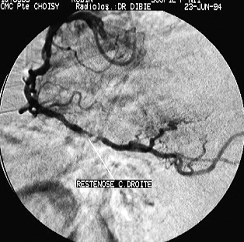

Figura 7. Coronarografie stanga a), dreapta b) stenoze multiple ateromatoase

Angiografia coronariana cu substanta de contrast efectuata la intervale de timp va arata gradul de evolutivitate al obstructiei coronariene si modul de dezvoltare a circulatiei colaterale (Dr. R. R. Mateescu, 2005).

Figura 8. angiografie coronariana: a) artera coronara normala; b) artera coronara cu ischemie.